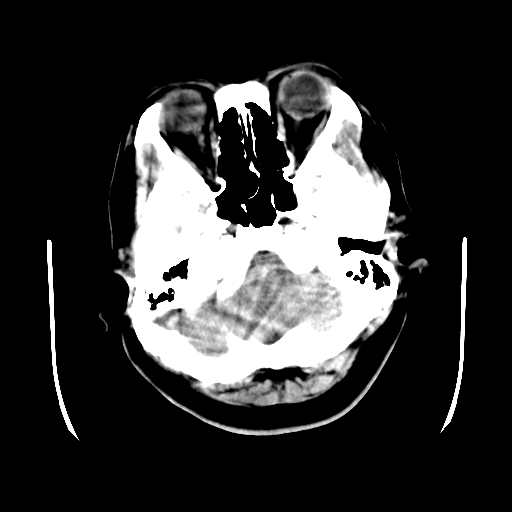

以下是引用cgf在2010-1-3 17:53:00的发言:[br]此病例多考虑:透明隔发育异常 透明隔囊肿可能性大;右侧基底节区(尾状核头)小片状低密度影考虑陈旧性腔梗[br][br]透明隔发育异常:包括透明隔间腔(第五脑室)、韦氏腔(第六脑室)、透明隔囊肿、透明隔缺如;前两者属于正常变异,后两者属于发育畸形;[br]透明隔间腔向下扩张形成韦氏腔;[br]有时透明隔间腔与透明隔囊肿很难鉴别;透明隔间腔间距一般不超过0.5cm,间距大于0.5cm时应考虑透明隔囊肿;[br]透明隔缺如为两侧脑室间隔缺如、融合成单脑室畸形,可伴有智力发育异常;[br][br]

以下是引用liaoqiang在2010-1-3 16:04:00的发言:[br]考虑侧脑室脉络丛囊肿?不除外变异的威氏腔。

以下是引用江广1996在2010-1-3 20:17:00的发言:[br]考虑变异的威氏腔。不除外侧脑室脉络丛囊肿.[br]透明隔囊肿大多数偏前,在侧脑室前角之间。